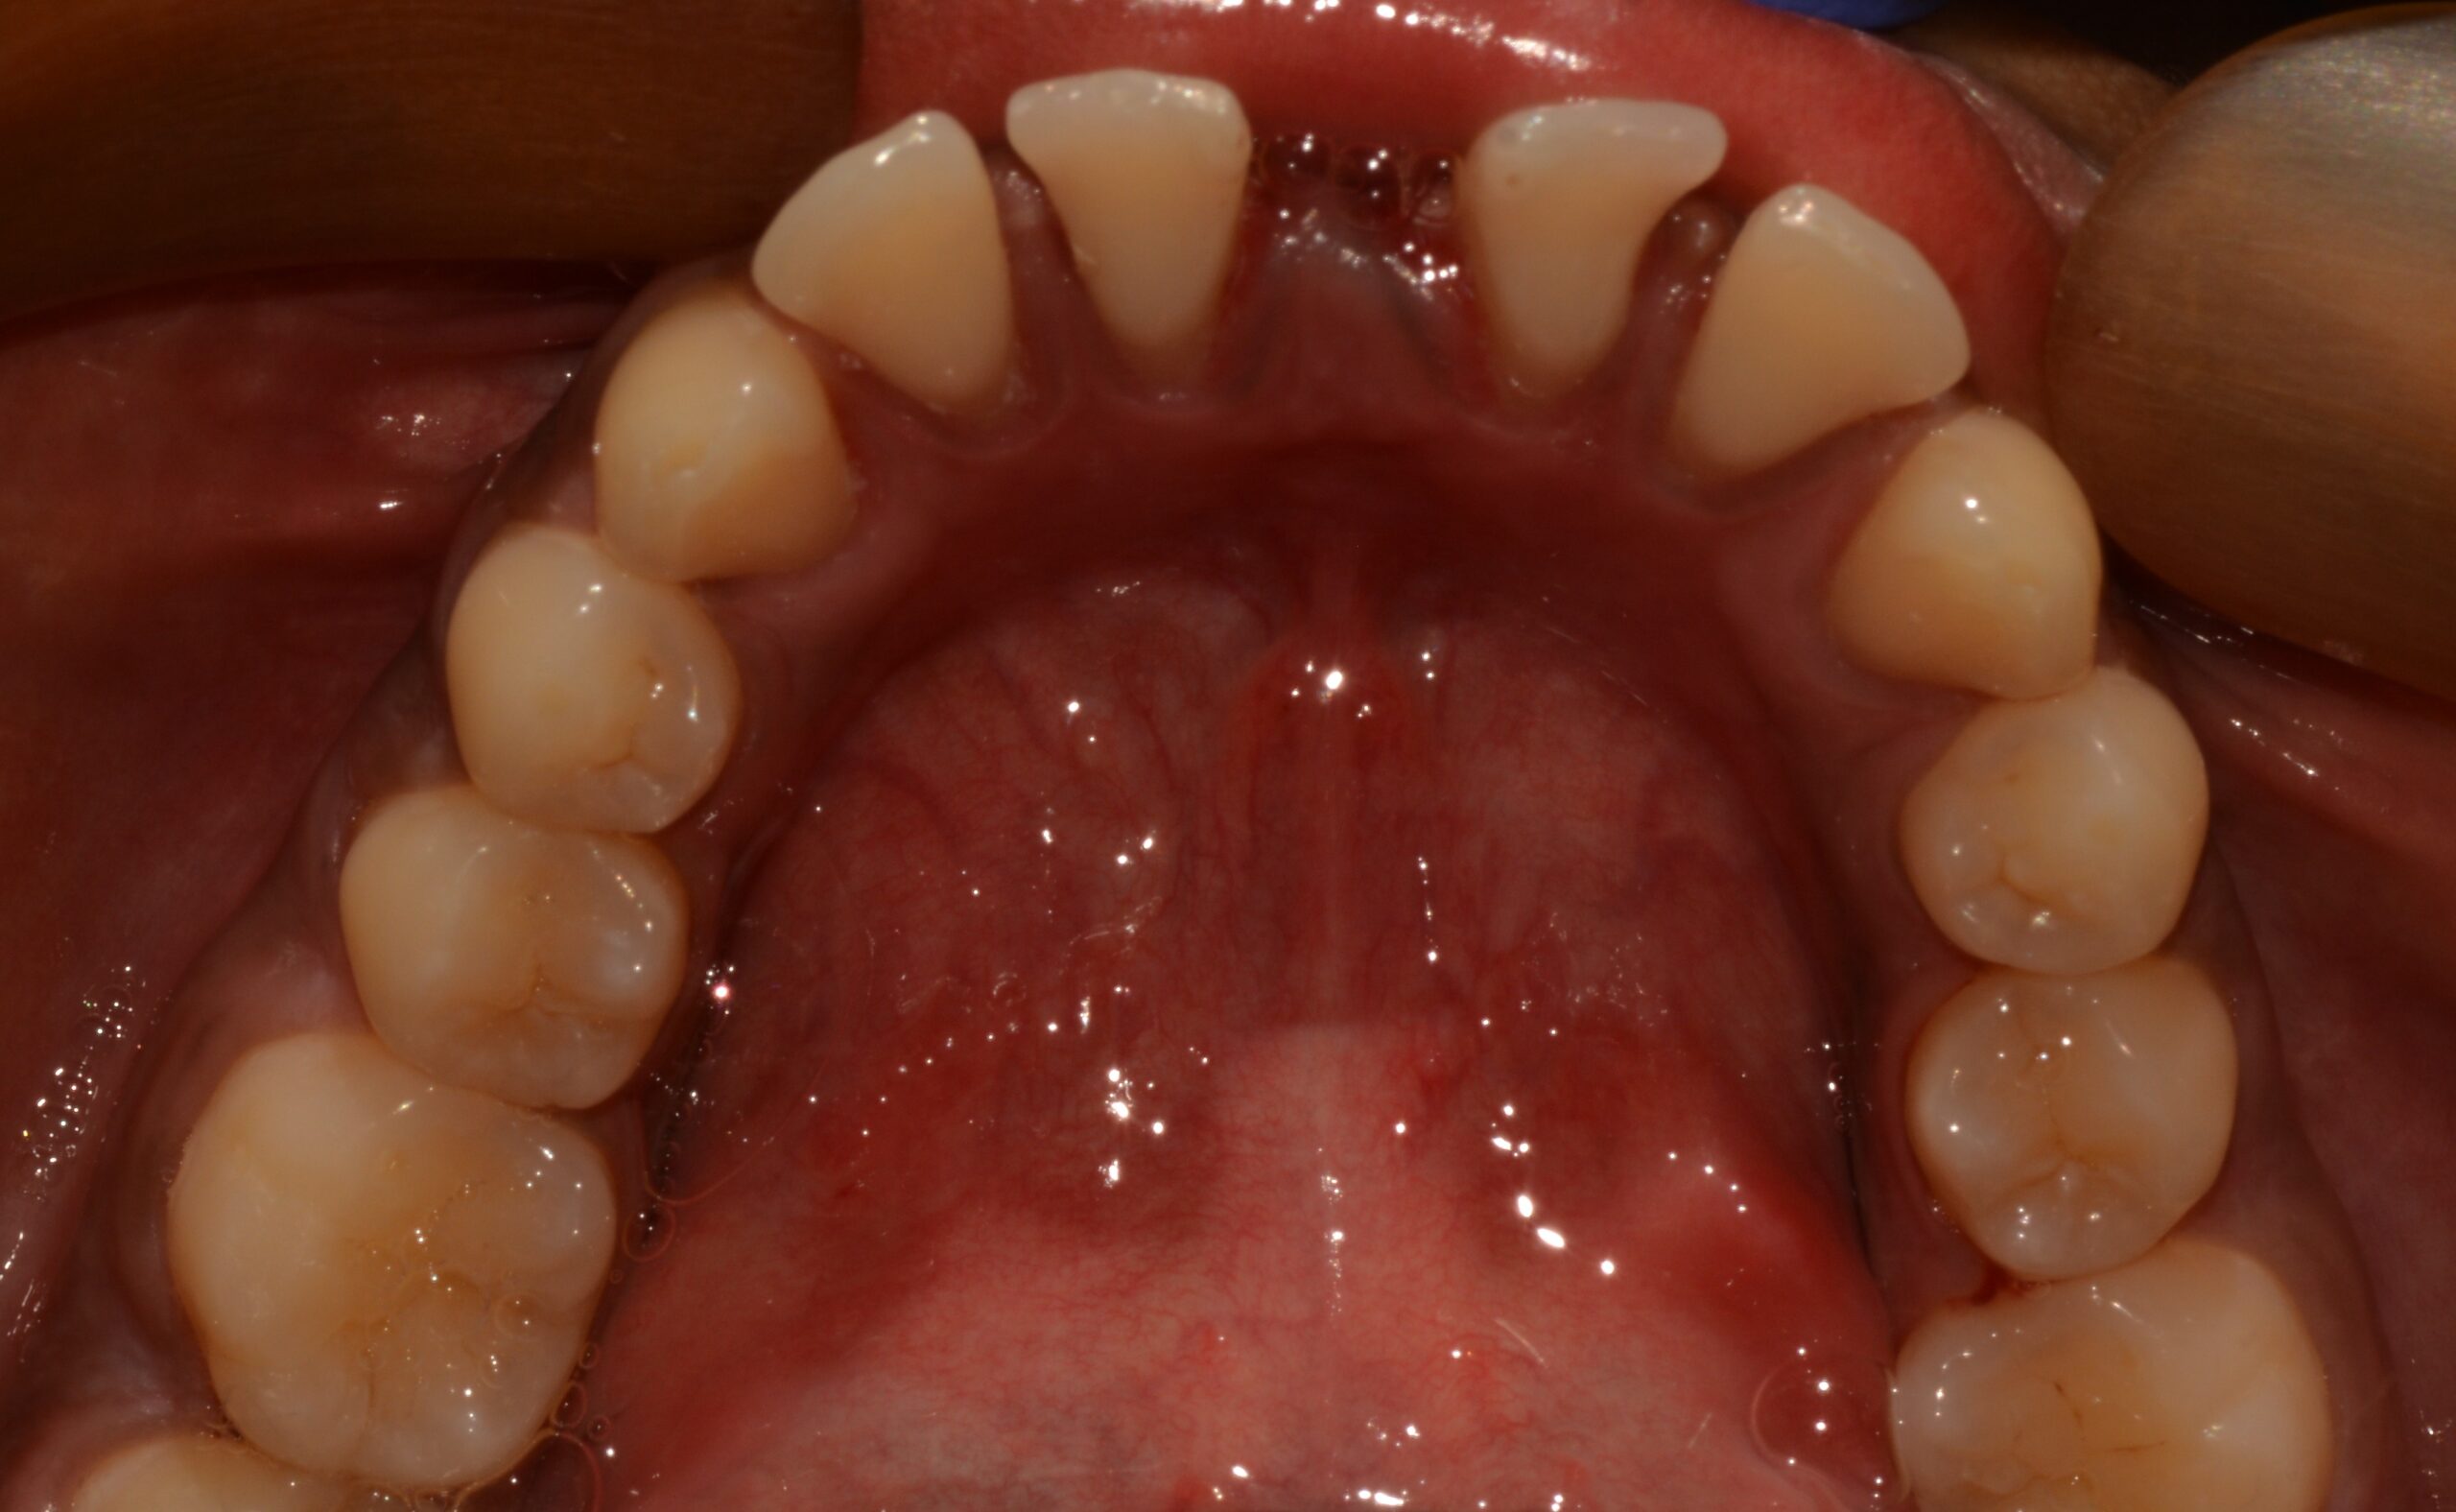

Before

After